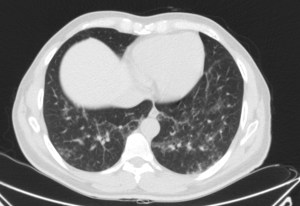

TAC: Vidrio deslustrado difuso y perihiliar frecuente, infiiltrado reticular, consolidaxión y patrón de árbol en brote, engrosamiento de septos, patrón en empedrado, derrame pleural, quistes.

Estos hallazgos descritos al pie de las radiografías son inespecíficos, pero al tratarse de un paciente inmunodeprimido, la primera posibilidad diagnóstica es una neumonía por Pneumocistis.

PNEUMONÍA POR PNEUMOCYSTIS (PCP).